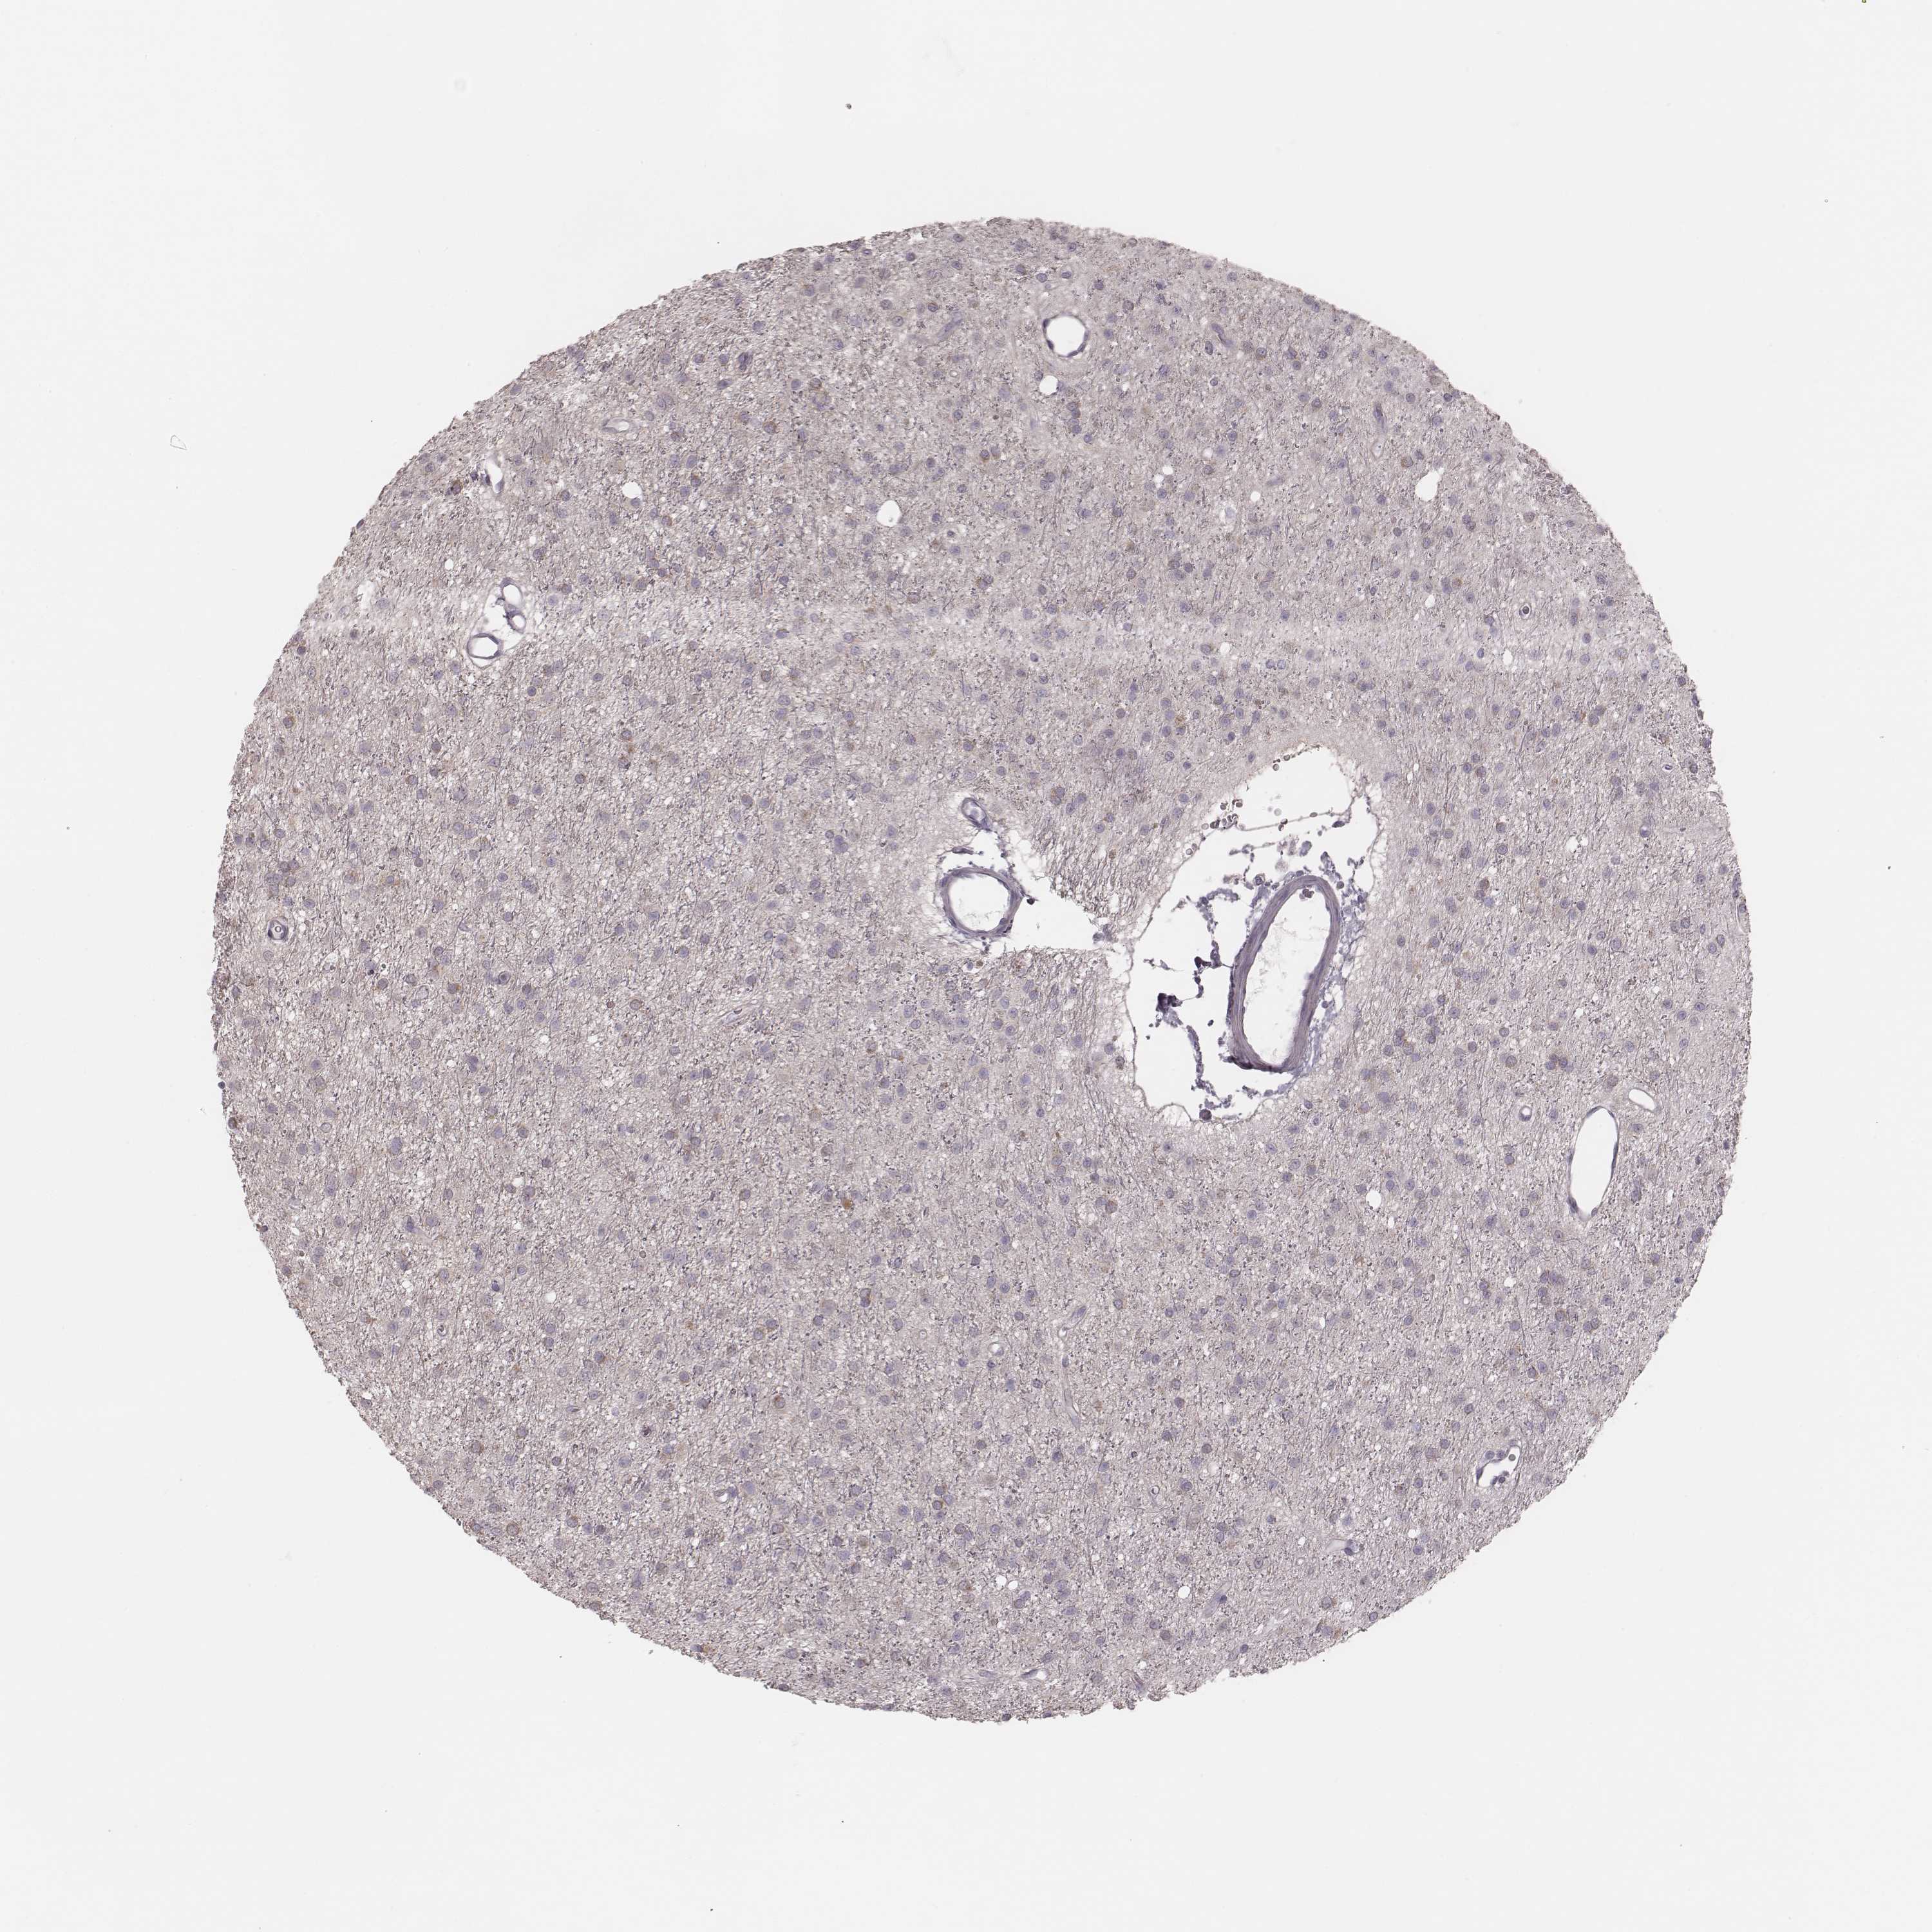

GLIOMA - Protein expressioni

A mouse-over function shows sample information and annotation data. Click on an image to view it in a full screen mode. Samples can be filtered based on level of antibody staining by selecting one or several of the following categories: high, medium, low and not detected. The assay and annotation is described here.

Note that samples used for immunohistochemistry by the Human Protein Atlas do not correspond to samples in the TCGA dataset.

Antibody stainingi

Antibody staining in the annotated cell types in the current human tissue is reported as not detected, low, medium, or high, based on conventional immunohistochemistry profiling in selected tissues. This score is based on the combination of the staining intensity and fraction of stained cells.

Each image is clickable and will lead to virtual microscopy that enables deeper exploration of all samples and also displays staining intensity scores, fraction scores and subcellular localization as well as patient and tissue information for each sample.

Antibody HPA035210

Antibody HPA062272

Glioma, malignant, Low grade

Glioma, malignant, High grade